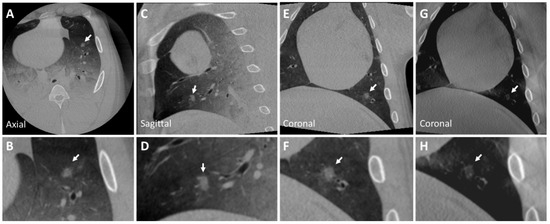

3.2. Post-Mortem Swine Lungs

| Diameter (mm) | CT Attenuation (HU) | |

|---|---|---|

| Lung Nodule | <30 | 50 (30) |

| Nodule 1 | 11 × 6.5 | |

| Nodule 2 | 8 × 7 | −360 (±55) |

| Nodule 3 | 10 × 9 | 25 (20) |

| Nodule 4 | 9 × 8 | −330 (50) |

| Nodule 5 | 16 × 12 | −310 ( |